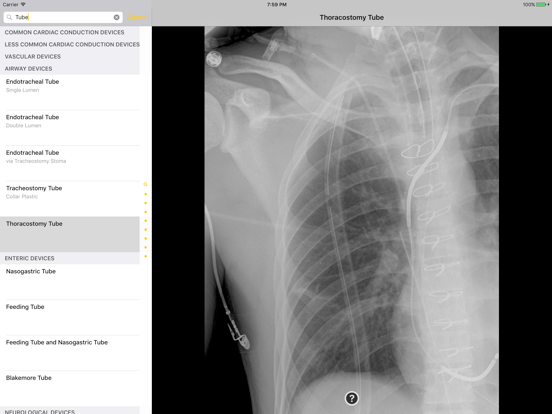

Introducing the Atlas of Medical Devices on Chest Radiography – one of the largest and most comprehensive collections of medical devices on chest radiography in existence. This app is an outstanding resource for physicians, physicians-in-training, and many healthcare providers who encounter medical devices on chest x-rays in daily practice. Review and explore the appearances of common and uncommon medical devices, organized by category. Search for a medical device in seconds using this app's lightning quick search feature.

· Countless images, organized into the following categories: Common Cardiac Conduction Devices, Less Common Cardiac Conduction Devices, Vascular Devices, Airway Devices, Enteric Devices, Neurological Devices, Musculoskeletal Devices, and Miscellanenous Devices.

· Tap the caption icon to read more about the device and to see it highlighted on the chest radiograph.

· Outstanding search engine returns items tailored to your interest, always appropriated categorized.